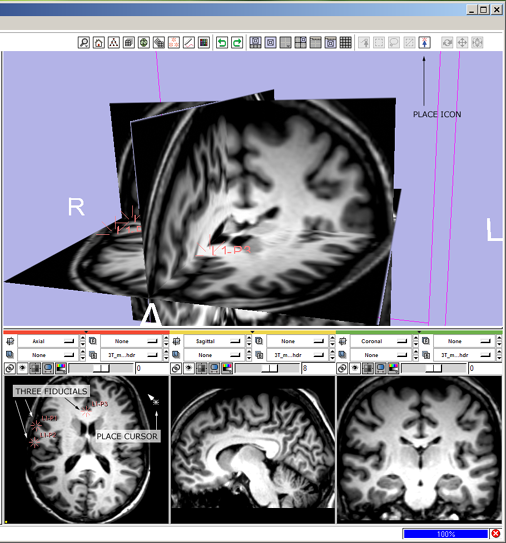

Below is how a user would use the mouse-mode interface to | Below is how a user would use the mouse-mode interface to | ||

tumble, track and dolly the camera to get the 3D View to look the way they like, and then put down three fiducial points and adjust their position. | tumble, track and dolly the camera to get the 3D View to look the way they like, and then put down three fiducial points and adjust their position. | ||

| − | 1 '''tumble:''' click the view tumble mouse-mode icon | + | 1(novice) '''tumble:''' click the view tumble mouse-mode icon |

* --> mouse-tumble icon highlights and all others deselect, cursor changes to indicate mouse-tumble mode. | * --> mouse-tumble icon highlights and all others deselect, cursor changes to indicate mouse-tumble mode. | ||

* then left-Click and drag in the 3D Viewer to rotate the view, | * then left-Click and drag in the 3D Viewer to rotate the view, | ||

| − | 2 '''track:''' click the view track mouse-mode icon [[image:ToolbarMousePan.png]] | + | 1(expert) '''tumble:''' ctrl+left-Click and drag in the 3D Viewer, |

| + | * --> mouse-tumble icon highlights and all others deselect; cursor changes to indicate mouse-tumble mode; view tumbles. | ||

| + | [[image:SB1.png]] | ||

Simple workflow storyboard

Below is how a user would use the mouse-mode interface to tumble, track and dolly the camera to get the 3D View to look the way they like, and then put down three fiducial points and adjust their position.

A novice user's workflow is described and an expert user's workflow using for the same simple task is given for comparison.

A novice user's workflow using these mouse-mode icons (top row: selected; bottom row: deselected):

1(novice) tumble: click the view tumble mouse-mode icon

- --> mouse-tumble icon highlights and all others deselect, cursor changes to indicate mouse-tumble mode.

- then left-Click and drag in the 3D Viewer to rotate the view,

1(expert) tumble: ctrl+left-Click and drag in the 3D Viewer,

- --> mouse-tumble icon highlights and all others deselect; cursor changes to indicate mouse-tumble mode; view tumbles.